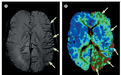

图 A 示左侧大脑半球皮质静脉扩张(箭头),图 B 示左侧大脑半球大面积灌注不足(箭头)。

患者入院后失语症逐渐消失,后续出现严重左侧搏动性偏头痛,了解病史发现患者有偏头痛家族史,结合 MRI 结果考虑诊断:偏头痛先兆期。

入院 10h 后复查 MRI 脑实质无异常,颞叶过度灌注明显,进一步诊断为:偏头痛先兆期延长。

本例患者的症状还是比较典型的:神经系统症状在几分钟内逐渐发展,从视觉障碍开始,随后出现感觉缺陷和语言障碍,最后是搏动性头痛。这种症状进展就要怀疑「偏头痛先兆期」。

本病 MRI 表现主要就是多血管区域灌注不足和皮质静脉扩张,一般无弥散或脑实质异常,也无血管闭塞。对于频繁发作的患者,可以在头痛先兆出现时立刻开始服用预防性药物,如 β 受体阻滞剂、钙通道阻滞剂、抗癫痫药物等,以减少头痛发作的频率和程度。